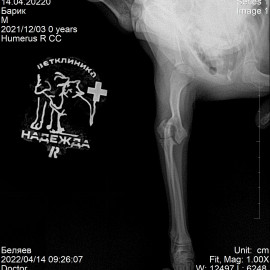

Пациент - собака по кличке Барик.

Обратились в клинику с жалобами на отсутствие опороспособности на правую переднюю лапу.

Были проведены осмотр и рентгенологическое исследование. Поставлен диагноз: перелом правого плеча. Проведена операция: остеосинтез правой плечевой кости.

Снимки 2-3 после операции.